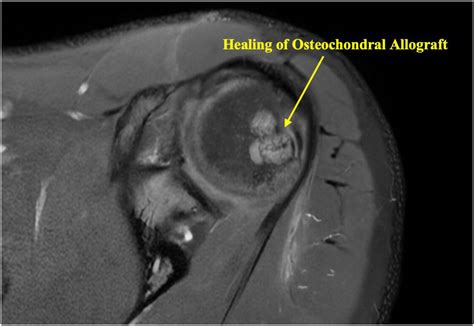

• Remplissage Procedure: A technique where the capsule and the infraspinatus tendon are sutured into the Hills Sachs lesion, effectively “filling” the defect and preventing it from catching.

• Bone Grafting: In cases of severe bone loss, surgeons may use a bone graft to restore the contour of the humeral head.

When assessing a patient, medical professionals often categorize the severity of the lesion based on the percentage of the humeral head involved. Lesions involving less than 20% of the humeral head are typically managed non-operatively, while those exceeding 30-40% almost always require surgical attention to restore structural integrity. Consistent monitoring by an orthopedic surgeon is essential to track whether the joint is becoming more unstable over time.